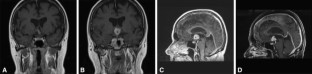

Fig. 1